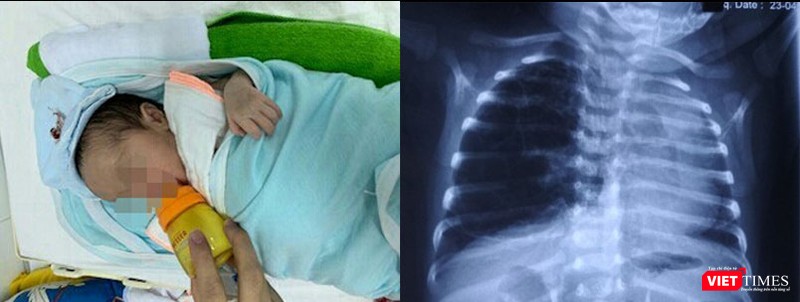

Ngày 13/5, TS. Nguyễn Việt Hoa - Trưởng khoa Phẫu thuật nhi và trẻ sơ sinh, Bệnh viện Hữu nghị Việt Đức, cho biết các bác sĩ đã cứu chữa thành công một em bé sơ sinh là Nguyễn D.A bị dị dạng đường dẫn khí phổi bẩm sinh. Nhờ đó, bé đã không còn biểu hiện của bệnh tật và bú mẹ bình thường.

Bé D.A bị dị dạng đường dẫn khí phổi bẩm sinh.

Theo TS. Nguyễn Việt Hoa, dị dạng đường dẫn khí phổi bẩm sinh là một trong những dị tật hiếm gặp ở trẻ, nhưng rất nặng nề. Dị dạng khiến trẻ bị khó thở, suy hô hấp, tràn khí màng phổi. Một phần của phổi thai nhi phát triển bất thường, có nhiều nang to, nhỏ khác nhau như chùm nho, nhưng không có chức năng hô hấp như phổi bình thường, dễ bị nhiễm trùng nhiều lần.

Khi mắc dị tật bẩm sinh này, trẻ phải phẫu thuật cắt bỏ nang dị tật. Tuy nhiên đây là ca phẫu thuật khó do trẻ còn nhỏ, phẫu trường hẹp, đòi hỏi phải có điều kiện về gây mê hồi sức, phẫu thuật viên có trình độ, khéo léo.